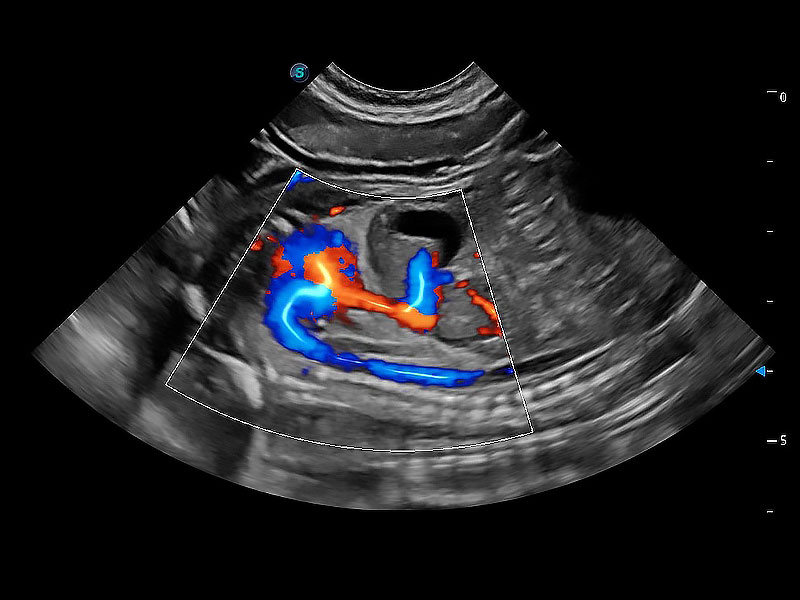

ProPet 80 配备了丰富的心脏探头群、先进的成像技术和专业的心脏测量工具,可帮助动物医生为不同体型和生理结构的动物提供心脏和心肌功能的全面评估。

实时用颜色表示心肌组织运动,观察和定量组织的运动情況,对快速检测与评估心肌的灌注和活性、电传导及心肌收缩和舒张功能等均能提供重要的诊断信息。